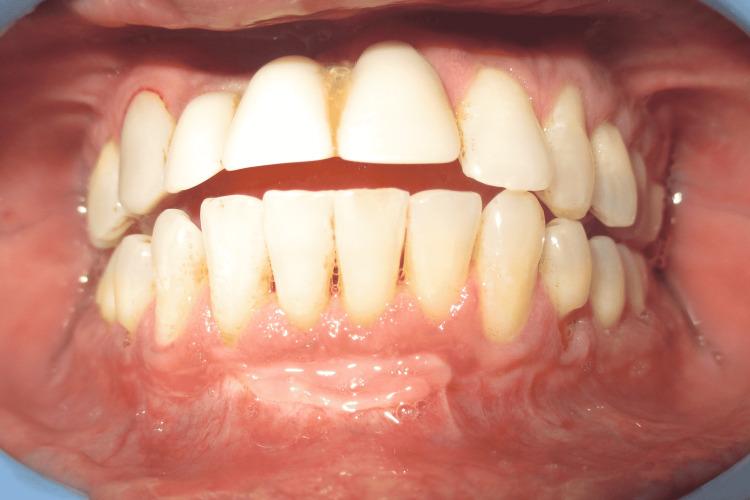

This case report describes Clark's technique of vestibuloplasty to treat shallow vestibule and, in addition, the use of free gingival autograft to augment attached gingiva to treat Miller's recession. Vestibuloplasty is performed to deepen a shallow vestibule. Different vestibuloplasty techniques are used to deepen the shallow vestibule by modifying the soft tissue attachment. A 29-year-old male presented to the Department of Periodontics and Oral Implantology, Regional Dental College, Guwahati, India with the chief complaint of bleeding from the lower anterior along with the gingival recession. Maintenance of regular oral hygiene was an added hindrance. The combined technique of vestibuloplasty and use of free gingival graft was performed to achieve dual benefits of increasing the vestibular depth and attainment of a thick gingival phenotype.

本病例报告描述了克拉克前庭成形术治疗浅前庭的技术,此外,还介绍了使用游离龈自体移植术增加附着龈以治疗米勒氏牙龈退缩的方法。前庭成形术用于加深浅前庭。通过改变软组织附着来加深浅前庭,采用了不同的前庭成形术技术。一名29岁男性因下前牙出血伴牙龈退缩,前往印度古瓦哈蒂地区牙科学院牙周病与口腔种植科就诊。保持规律的口腔卫生是一个额外的障碍。采用前庭成形术和游离龈移植术相结合的技术,以实现增加前庭深度和获得厚龈表型的双重益处。